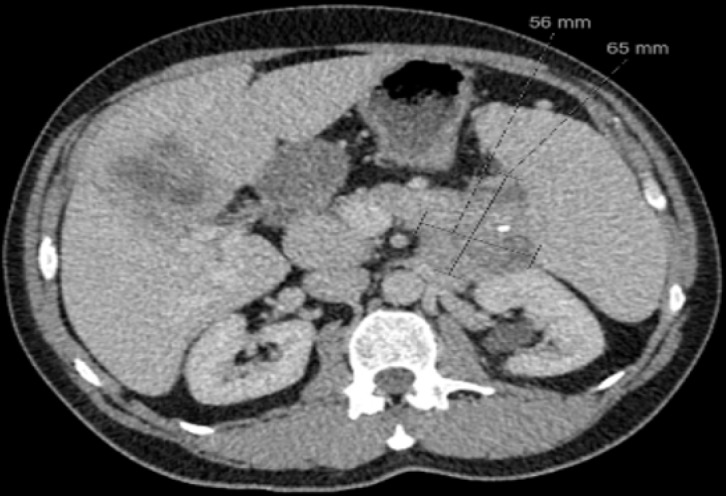

胰腺神经内分泌肿瘤(pNETs)是罕见的,在及时诊断和后续治疗方面提出了重大挑战。这些肿瘤的临床和病理生物学行为差异很大,使得临床医生的随访和治疗方法具有挑战性。虽然这些肿瘤大多数是激素不活跃的,但有些可能与内分泌功能障碍有关。非常罕见的是,非功能性肿瘤后来会变得激素活跃,进一步使预后和治疗复杂化。根据疾病的特点、临床表现和预后,制定了不同的治疗方式,效果也各不相同。我们最近遇到了一个独特的晚期无功能恶性pNET病例,诊断为转移性疾病,医学上使用生长抑素类似物治疗(奥曲肽)和靶向治疗(依维莫司),病情稳定40个月,随后变成功能性(胰岛素瘤)。在这一独特病例的帮助下,我们在这篇基于证据的综述中更新了目前pNETs的临床、诊断和治疗方法。

Pancreatic neuroendocrine tumors (pNETs) are rare, presenting significant challenges in timely diagnosis and subsequent treatment. The clinical and pathobiological behavior of these tumors varies significantly, making follow-up and therapeutic approaches challenging for clinicians. Although the majority of these neoplasms are hormonally inactive, some can be associated with endocrine dysfunction. Very rarely, a nonfunctional tumor can later become hormonally active, further complicating prognostication and management. Depending on the character of the disease, clinical picture and prognosis, different treatment modalities are instituted with varying effectivities. We recently came across a unique case of nonfunctioning malignant pNET at an advanced stage, metastatic disease upon diagnosis, managed medically with somatostatin analog therapy (Octreotide) and targeted therapy (Everolimus) with stable disease for 40 months that subsequently turned out to become functional (insulinoma). With the aid of this unique case, we update the current clinical, diagnostic and therapeutic approach to pNETs in this evidence-based review.